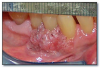

Inflammatory papillary hyperplasia (Figure 52) represents an overgrowth of epithelial and fibrous connective tissue, usually as a response to chronic irritation from a denture. The lesion occurs on the hard palate or mandibular alveolar mucosa underneath a denture. The surface of the lesion is bumpy, nodular, or velvety, and often erythematous. The patient may complain of pain or burning in association with the lesion, or the lesion may be asymptomatic. Lesions often have concomitant overgrowth of candidal organisms. The patient should remove the denture as much as possible, and the lesion should be reevaluated. If the papillary overgrowth is minimal, the lesion does not need to be removed. More extensive lesions should be excised. The denture should be remade and the patient educated about removing the denture at night and cleaning the denture. If candidosis is present it should be treated with a topical antifungal ointment or cream applied to the inner surface of the denture.